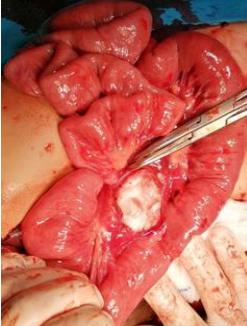

After admittance and after regular preoperative preparation (laboratory findings, radiological diagnostics – head, thorax, abdominal CT and consultation of various specialists), the same day after admission) the condition of hemorrhagic shock was verified and under general anesthesia, urgent surgical procedure was performed. The surgery was done as a vital indication due to clinical signs of hemorrhagic shock. A medium laparotomy was chosen as the surgical approach and in abdominal cavity greater amount of fresh blood subhepatic right, paracolic on both sides, perihepatic, perisplenic and interintestinal was seen. The blood was evacuated and detailed exploration was done which pointed to subcapsular lesion of the spleen on the convexity in the middle part which did not bleed, hematoma of the lower part of spleen with incomplete demarcation to other tissue, traumatic liver lesion on the incision that is shallow, about 2 cm long, of slight depth, did not bleed or had a biliary leak; the second lesion is next to the fundus of the gallbladder just below the free edge of the liver, it is about 4 cm long and 1 cm deep, did not bleed actively or had biliary leak; the gallbladder was contused with a hematoma of the medial wall without elements of compression of the duct (Figure 7);

Figure 7: The lesion is next to the fundus of the gallbladder just below the free edge of the liver, it is about 4 cm long and 1 cm deep, did not bleed actively or had biliary leak; the gallbladder was contused with a hematoma of the medial wal without elements of compression of the duct.

Traumatic lesion of the mesentery about 55 cm from Treitz with rupture of a bleeding blood vessel leading to a larger hematoma retroperitoneally on the left; the injury is taken care of by suture; lesion of the mesentery at about 70 cm with lesion of vascular branches with active bleeding (Figure 8);

Figure 8: Traumatic lesion of the mesentery about 55 cm from Treitz with rupture of a bleeding blood vessel leading to a larger hematoma retroperitoneally on the left; the injury is taken care of by suture

Traumatic rupture of the mesocolon in its half with a Riolan's arch lesion and consequent bleeding (Figure 9). The same is taken care of by blood vessel ligatures.

Figure 9: Lesion of the mesentery at about 70 cm without lesion of vascular structures; traumatic rupture of the mesocolon in its half with a Riolan's arch lesion and consequent bleeding. The same is taken care of by blood vessel ligatures.